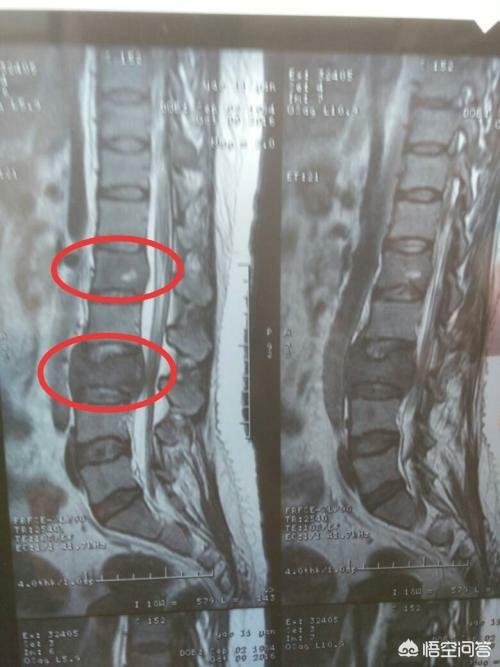

Bien qu'il existe certaines caractéristiques de la douleur chez les patients atteints de métastases osseuses dues à un cancer, vous pouvez également constater que certains symptômes interfèrent avec la maladie courante.Si le patient se produit, la métastase osseuse de la colonne vertébrale stimule les nerfs, il est alors facile pour le médecin ou le patient de mal diagnostiquer les symptômes induits par la hernie discale, et à ce moment-là, en tant que patient, le corps a des anomalies, nous devrions demander l'aide du médecin en temps opportun, et en tant que médecin d'essayer de communiquer avec le patient, de faire quelques examens relativement de haute qualité, essayer d'écarter le risque de métastase osseuse, comme pour les douleurs dorsales à long terme des personnes âgées, nous recommandons souvent que l'IRM au lieu de l'examen radiographique, et le mal de dos du patient, le mal de dos du patient est très élevé. Par exemple, pour les personnes âgées souffrant de lombalgies chroniques, nous recommandons souvent de leur faire passer une imagerie par résonance magnétique (IRM) plutôt qu'une radiographie.

Quel type de douleur doit alerter sur la présence de métastases osseuses ? Les métastases osseuses sont une manifestation fréquente des tumeurs malignes à un stade avancé. La tumeur primaire présente dans d'autres parties du corps se métastase dans les os par les voies sanguines et lymphatiques, formant ainsi des métastases osseuses. Les métastases osseuses signifient que le tissu osseux normal a été détruit et remplacé par du tissu tumoral. Les métastases osseuses peuvent être classées en trois types selon la spécificité de la lésion : le type ostéolytique, le type ostéogénique et le type mixte. Les sites courants de métastases osseuses sont l'os de la diaphyse moyenne (colonne vertébrale et bassin), les côtes et la métaphyse inférieure, l'os de la diaphyse moyenne étant le plus courant, ce qui est lié aux caractéristiques de l'apport sanguin dans cette zone. Comme le montre le cercle ci-dessous, les métastases osseuses sont multiples et la colonne vertébrale est en mauvais état.

Un homme de 46 ans a été vu en consultation pour une douleur persistante dans le bas du dos. On pensait que cette douleur était due à une hernie discale. Une radiographie a été effectuée et n'a révélé aucune anomalie. Les métastases osseuses provoquant une légère destruction osseuse sont invisibles à la radiographie, de même qu'une hernie discale. Je n'ai donc pas particulièrement pensé à la possibilité d'une métastase. Une semaine plus tard, comme il n'y avait toujours pas d'amélioration, il est venu passer un scanner et a découvert qu'une vertèbre lombaire avait été rongée. En voyant une telle image, le médecin spécialiste de l'imagerie a dû penser à la possibilité de métastases et a suggéré au patient de passer un scanner du thorax, et effectivement, il y avait une masse dans les poumons, qui a été considérée comme une métastase osseuse d'un cancer du poumon, ce qui a été confirmé par la pathologie plus tard.

Il a dit qu'il fallait faire un scanner amélioré et c'est ce qu'il a fait. Pour déterminer s'il s'agit d'une métastase osseuse. J'ai fait une scintigraphie osseuse et une IRM. Il s'agit d'une métastase osseuse ! Donc, tous ceux qui ont une douleur fixe depuis plus d'un demi-mois devraient aller à l'hôpital pour vérifier !

Montrant un cancer avec métastases osseuses survenant dans la colonne vertébrale thoracique